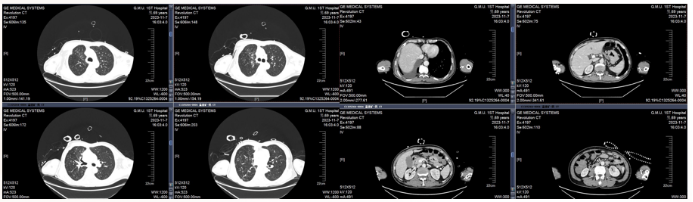

胸部影像学提示肺炎有所控制,10月27日胸部CT提示右下肺实变(图2)

图片

2  胸部影像学变化